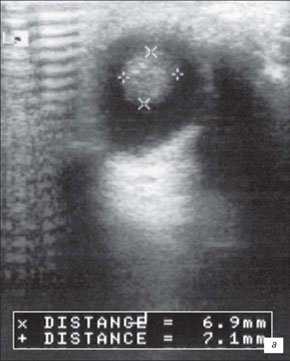

На первом месте по простоте использования и быстроте получения информации стоит УЗИ. Исследование позволяет достаточно быстро отдифференцировать ретинобластому от неопухолевых образований. Ретинобластома имеет характерные ультразвуковые признаки. При А-сканировании определяется высокоамплитудный эхосигнал с аттенуацией в нормальных тканях орбиты. По нашим данным, при В-сканировании с частотой излучения не менее 5-7 Мгц визуализируется округлое или неправильной формы внутриглазное образование с отложениями кальция. Образование исходит из задних отделов глаза, хорошо отграничено от стекловидного тела (рис. 1). Кровоток в опухоли не определяется. Эхографические исследования особенно показаны в динамике для оценки реакции опухоли на радиотерапию. Ультразвуковая картина опухоли весьма близка к так называемым псевдоопухолям сетчатки - гранулематозном изменении сетчатки, например, при токсокарозе. Безапелляционное заключение в совокупности с некритическим восприятием картины глазного дна по данным офтальмоскопии может привести к абсолютно не показанной энуклеации.

а) Небольшая ретинобластома. В ткани опухоли видны более плотные мелкие структуры (включения кальция).